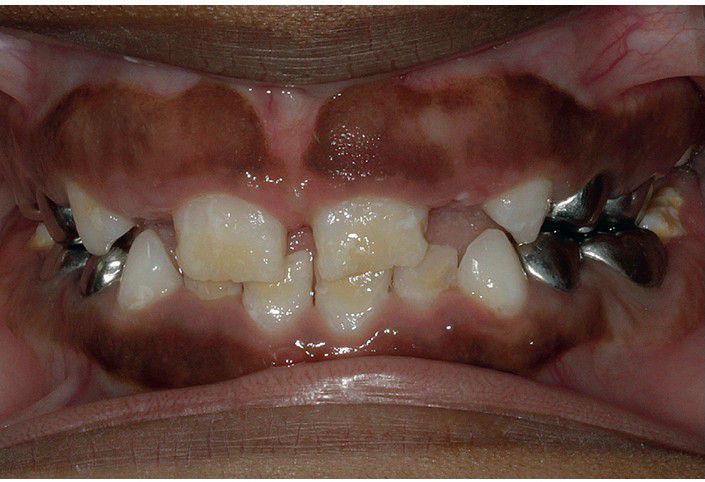

Hypocalcification of the teeth is seen in this child who had vitamin D deficiency related to a diet of breast milk exclusively and lack of adequate sunlight exposure.